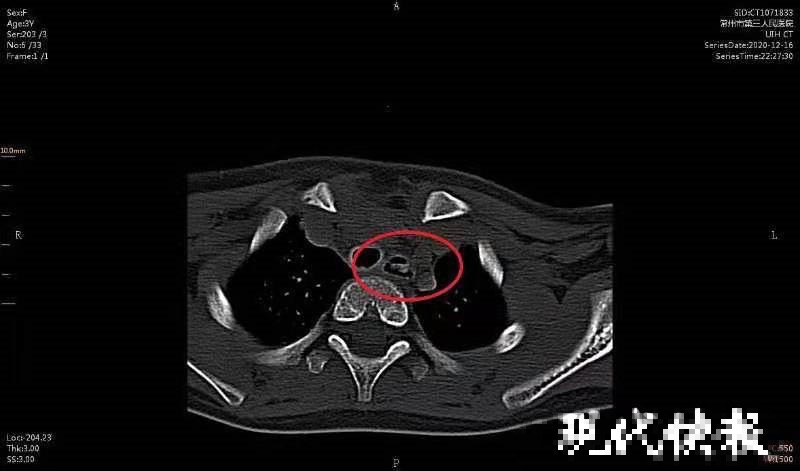

醫生經檢查後發現,有異物被卡在歡歡的食道內。據常州三院耳鼻咽喉科副主任醫師陸曉宇解釋指,食道內有3處最容易引起異物嵌頓的狹窄部位,包括咽與食管的交接處、左主支氣管後方與之交叉處,以及食管通過膈肌的裂孔處。經過急診手術後,醫生終於順利取出卡在歡歡食道的異物,並發現該異物竟然是一個黃色的「比卡超」玩具。其父母此時才發現女兒並非被食物嗆着,因此甚為自責。